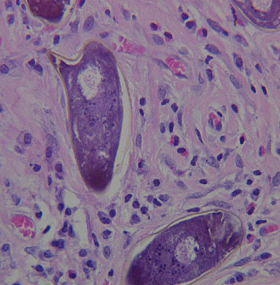

H&E stain of liver tissue

40X magnification

40X magnification